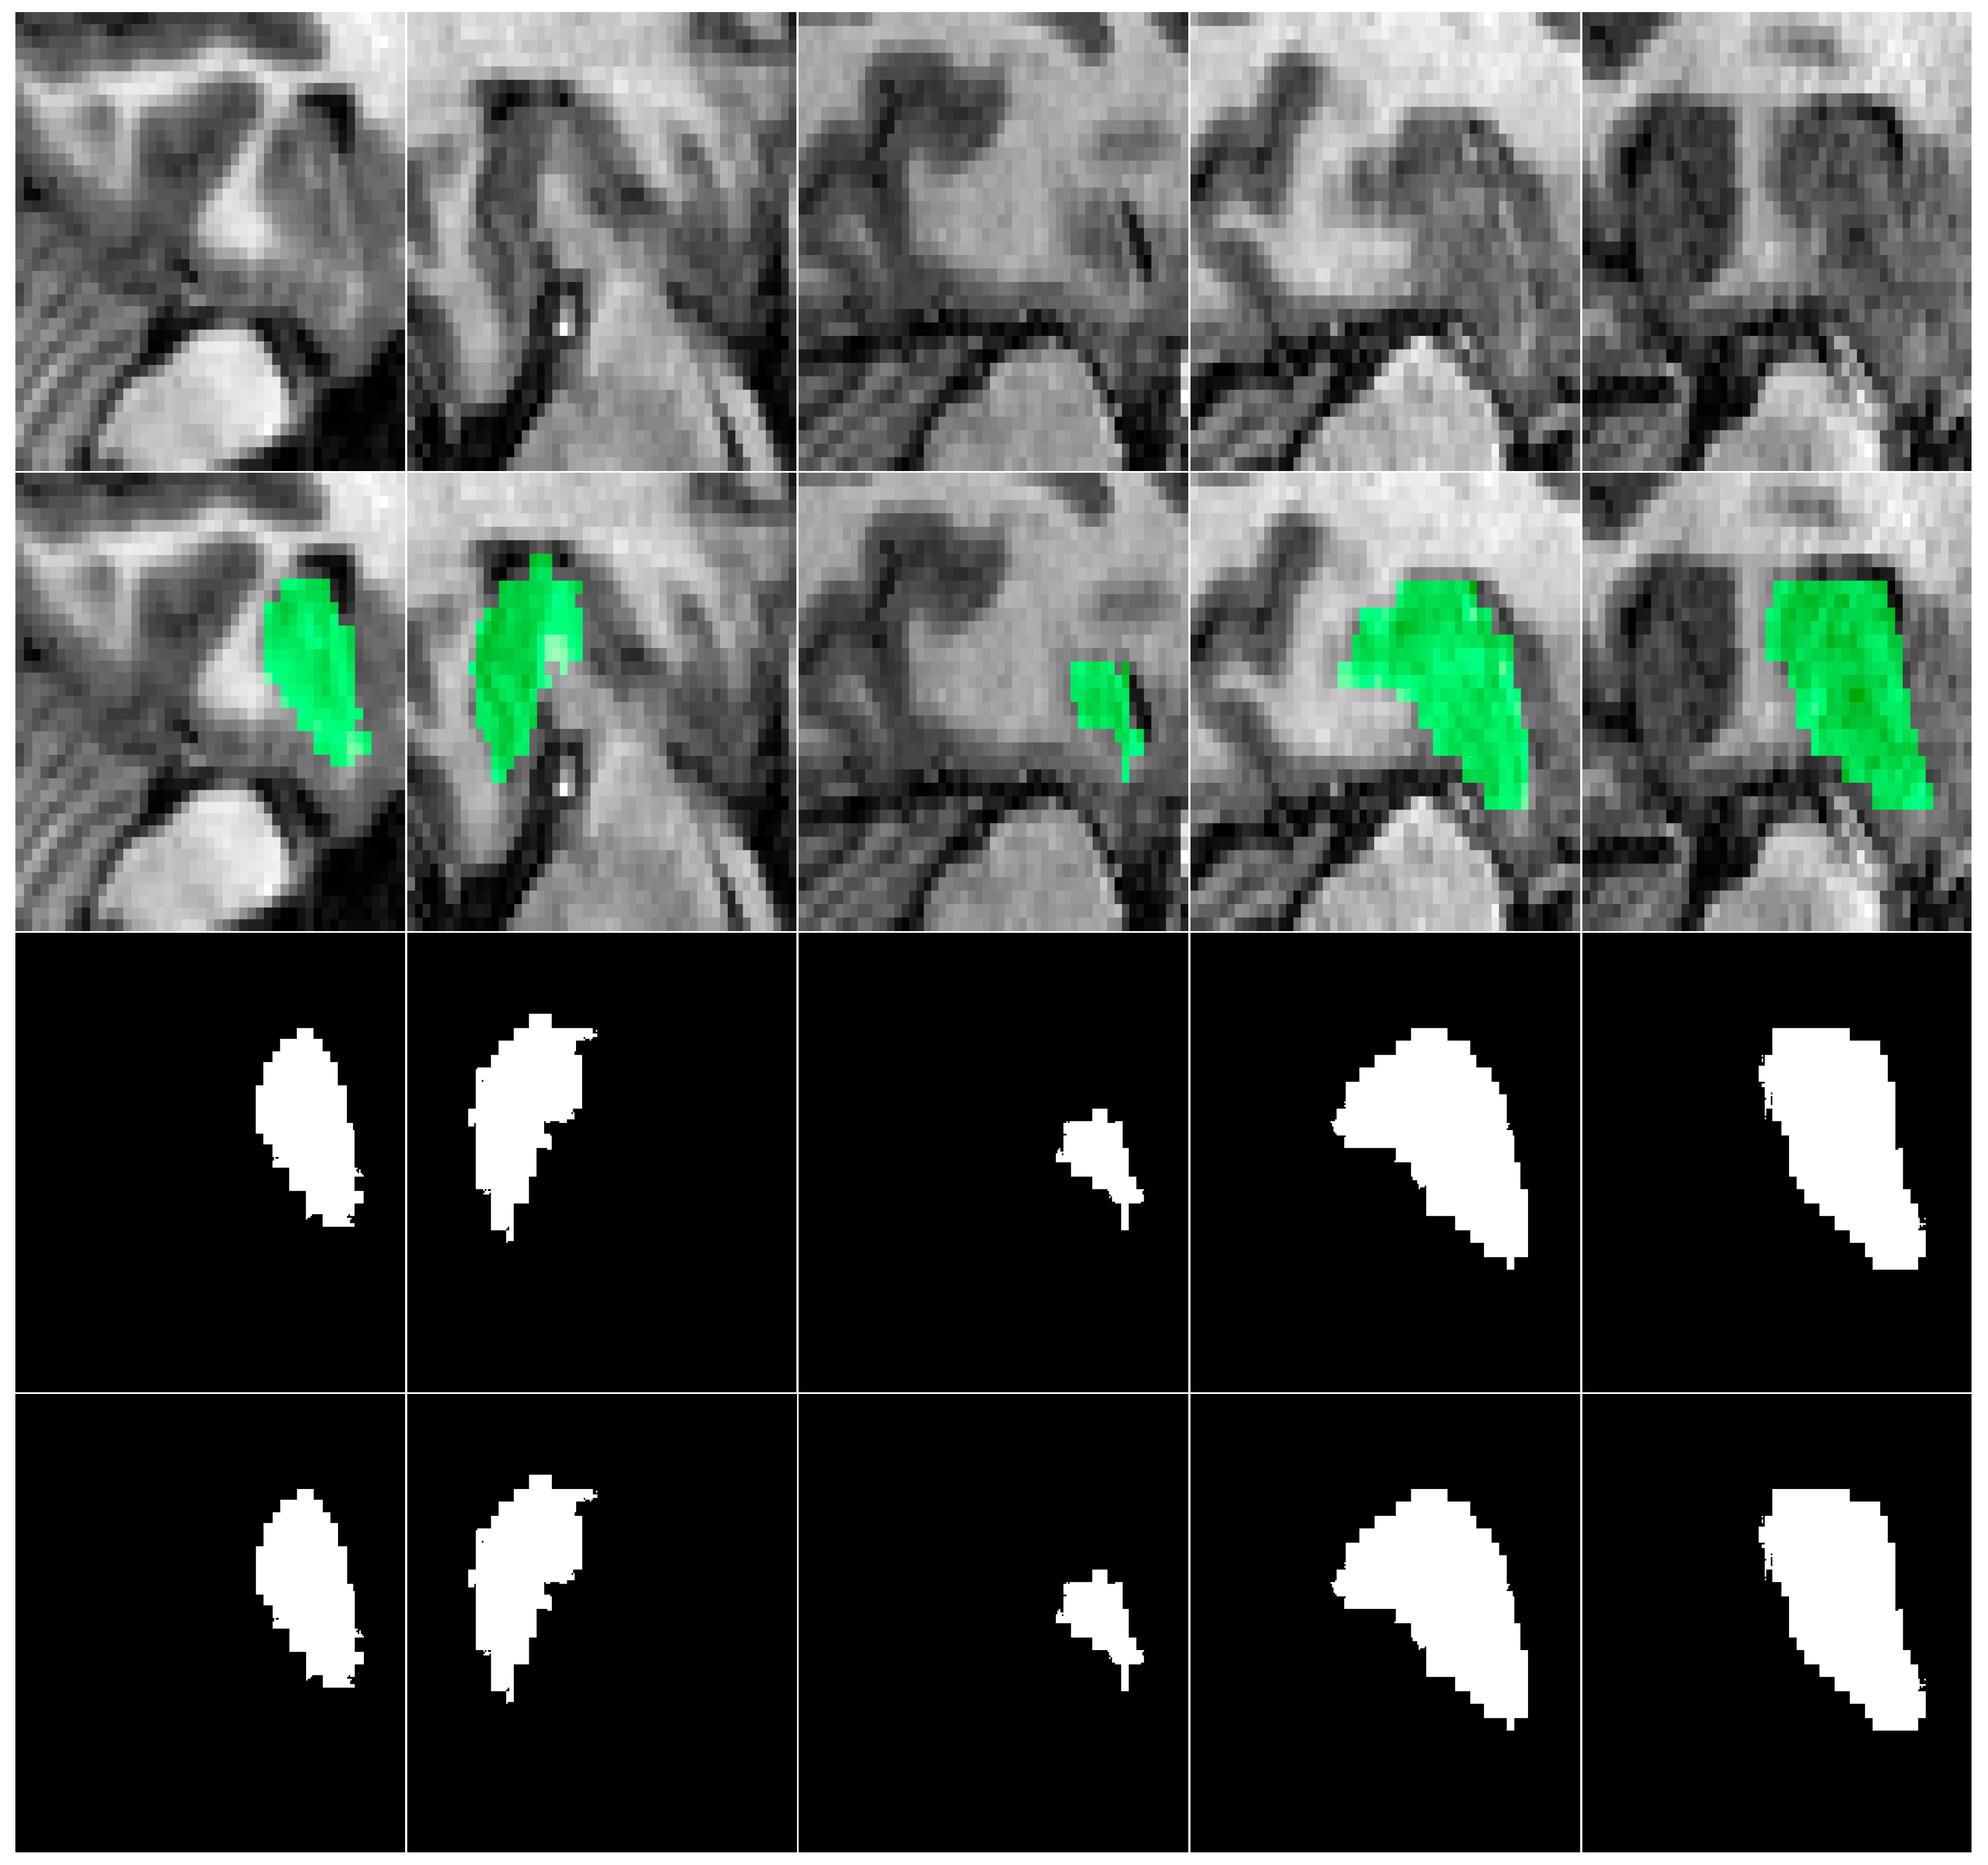

For empirical validation, we employed two hippocampus segmentation datasets: the Alzheimer’s Disease Neuroimaging Initiative (ADNI) dataset [34] and the Decathlon Hippocampus dataset [35]. Both datasets contain T1-weighted MRI scans and are publicly accessible resources for advancing Alzheimer’s Disease understanding and early diagnosis. The ADNI dataset comprises cross-sectional T1-weighted MRI scans from 135 subjects, with each subject contributing 189 axial slices (30 slices containing visible hippocampal structures on average). For model training and evaluation, data from 100 subjects (18,900 images) were allocated to the training set, while the remaining 35 subjects (6615 images) formed the test set. The Decathlon Hippocampus dataset includes T1-weighted MRI scans from 390 patients, with 30–34 slices per patient (9–10 slices with masks). The dataset was split into 260 patients (9270 images) for training and 130 patients (4499 images) for testing. Table 3 summarizes the ADNI and Decathlon datasets used for hippocampus segmentation in our experiments. A representative visualization of hippocampal ground truth annotations overlaid on corresponding MRI slices from the ADNI dataset is presented in Figure 5. This rigorously annotated dataset provides a robust foundation for benchmarking hippocampus segmentation models, particularly in the context of neurodegenerative disease assessment and clinical deployment.

Figure 5. Axial MRI slices (top), mask overlays (middle), and ground truth (bottom) for the hippocampal gyrus at slices 71st, 76th, 81st, 86th, and 91st.